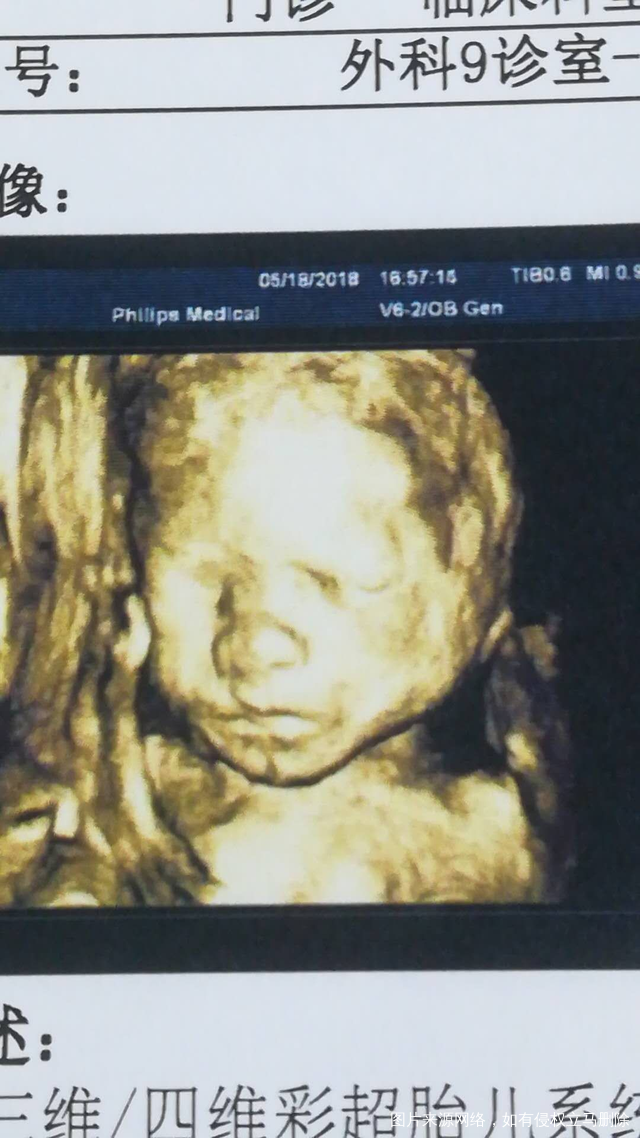

姐妹们:刷脸看男女啦!

2018-05-18 17:04:34